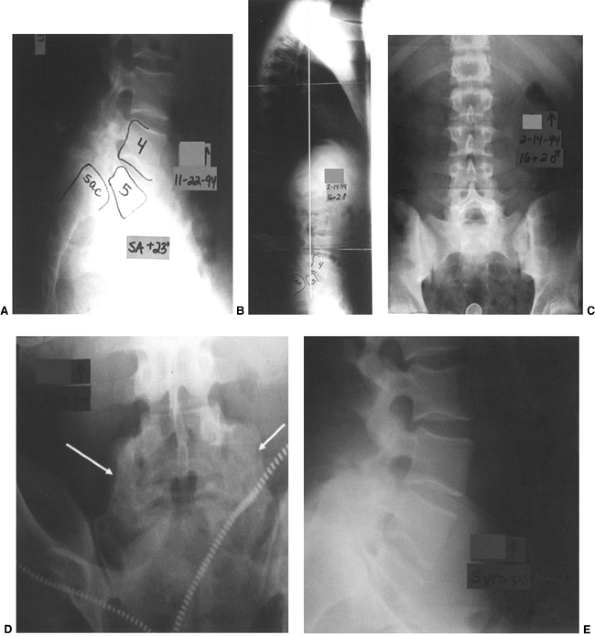

![]() |

Figure 21.14

This 16-year-old boy had a grade III isthmic spondylolisthesis at L-5–S1. He had chronic lumbosacral back pain without radicular pain. He was treated with a bilateral Wiltse paraspinal approach, with autogenous iliac crest bone graft placement following decortication from L-4 to the sacral ala. Postoperatively, he was maintained in a bilateral pantaloon cast for 3 months, and then in a lumbar-sacral orthosis for an additional 3 months. A: Preoperative lateral x-rays of a Grade III slip with a +25° angle. B: Upright long cassette lateral x-ray showing good overall sagittal balance. C: Preoperative frontal x-ray showing large lumbar transverse processess. D and E: At 5 years postoperatively, he had a rock-solid fusion from L-4 to the sacrum, with stable alignment in his lateral view radiograph. His pain was totally relieved postoperatively. |